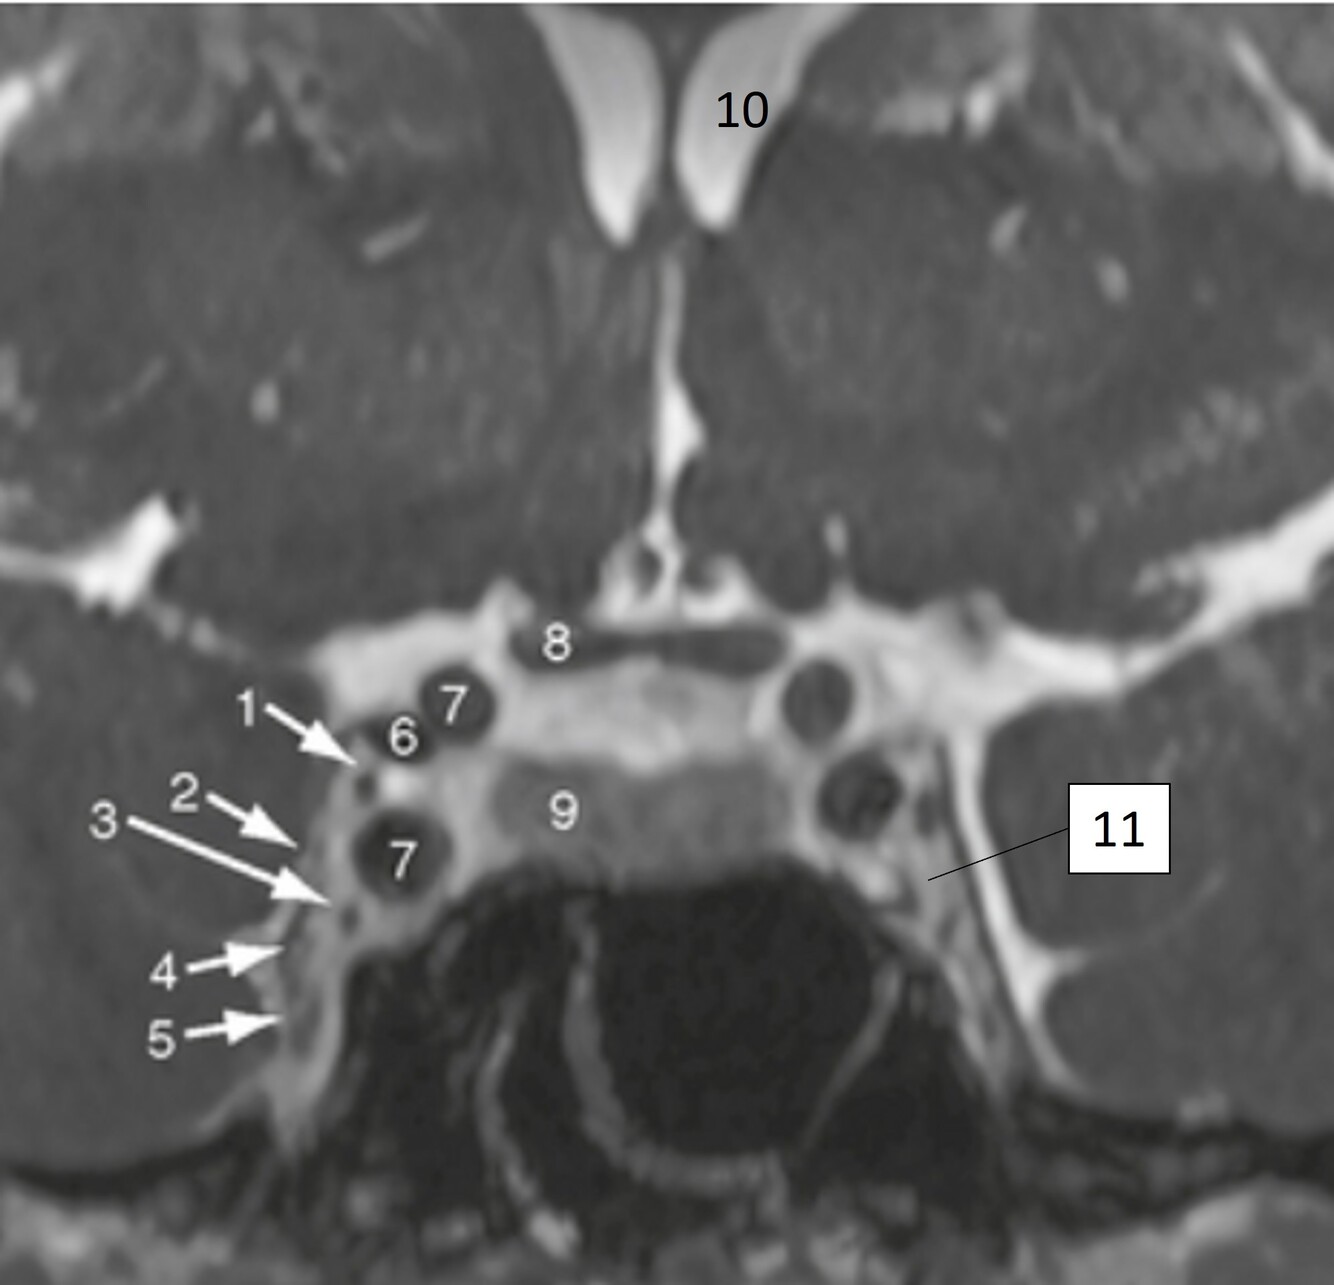

Q

Label 7-11

A

7=Rt Internal carotid artery

8=Optic chiasm

9=Pituitary gland

10-Lt lateral ventricle

11=Lt Cavernous sinus